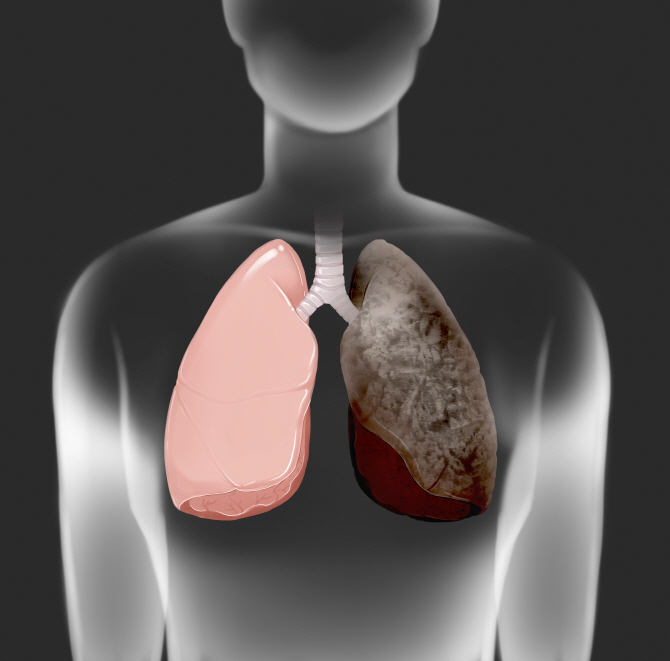

폐렴 증상 폐렴 증상

폐렴 증상 3. 호흡 곤란 및 숨 가쁨

폐에 염증이 생기면 산소 교환이 어려워져

숨이 차고 가슴이 조이는 느낌,

또는 평소보다 가쁜 숨, 짧은 호흡이 나타날 수 있어요.